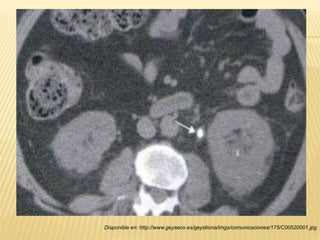

“TOMOGRAFÍA COMPUTARIZADA”

 Visualización del riñón y las vías de excreción

(uréteres) en un plano coronal.

 Estructuras peritoneales y retroperitoneales.

 Pacientes con cólico renal agudo.

 Sin contraste intravenoso.

 Distinguir cálculos uretrales distales de

“flebolitos”

Disponible en: http://www.geyseco.es/geystiona/imgs/comunicaciones/175/C00520001.jpg